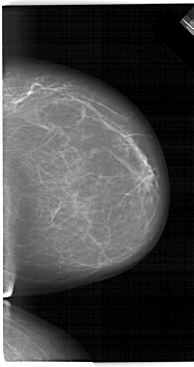

A_1464_1.RIGHT_CC

RIGHT_CC LINES 6601 PIXELS_PER_LINE 3481 BITS_PER_PIXEL 12 RESOLUTION 43.5 NON_OVERLAY